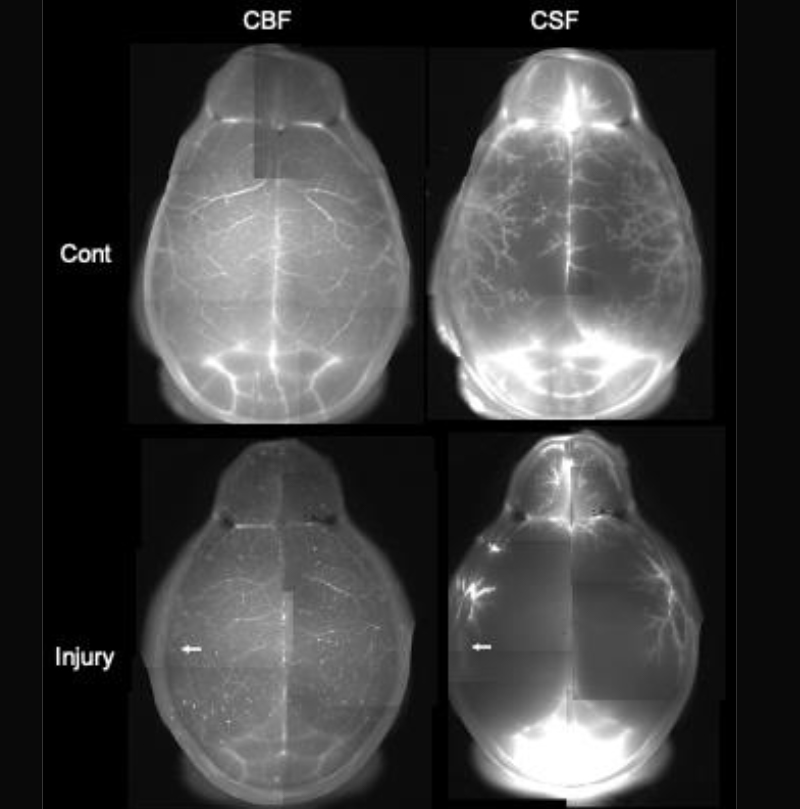

(b) Cerebral blood flow (CBF) and CSF after photo-injury